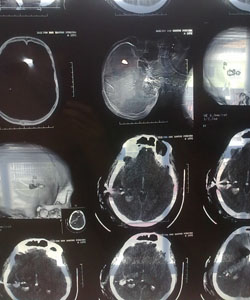

Luiz Mendonça, foi levado à Unidade de Tratamento Intensivo (UTI) do Huse onde está sendo mantido em coma induzido. No primeiro exame feito pela equipe de neurocirurgia, o paciente encontrava-se sedado, entubado, acoplado à ventilação mecânica e em coma. Havia ferimento penetrante do crânio em região parietal e transfixante em mão esquerda. O quadro clínico do paciente era grave com sinais de sofrimento encefálico. Ele foi imediatamente encaminhado ao centro cirúrgico para descompressão do crânio e correção das lesões decorrentes do ferimento penetrante. Até ontem, 18 à noite, o paciente mantém-se em estado grave.(Infonet).Ao lado uma das tomografias do crânio do motorista.